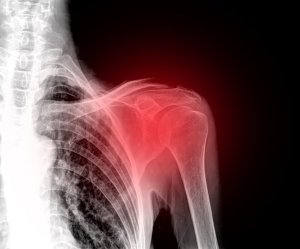

Smerter i skuldrene er en svært ubehagelig og hemmende tilstand siden skulderleddet er det som gjør oss mobile og gjør at vi effektivt kan bevege oss i omgivelsene våre.

Det finnes forskjellige typer skader som kan forårsake smerte, betennelse og manglende evne til å bevege seg. I tillegg kan en betennelse utvikle seg til å bli kronisk hvis vi ikke behandler det i tide.